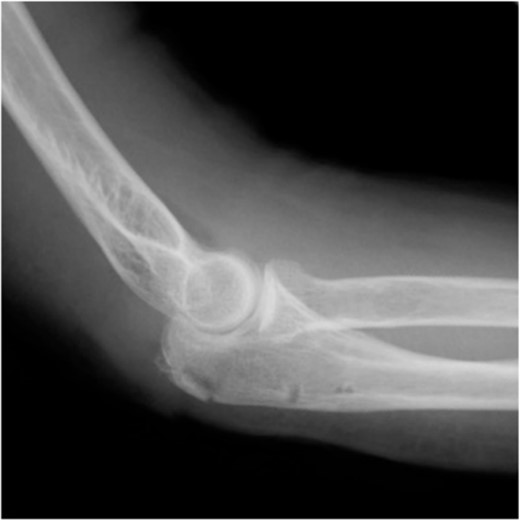

Postoperative radiography revealed reduced bone fragmentation (Fig. 5). The elbow was immobilized at 90° for 1 week postoperatively; range-of-motion exercises were started in postoperative week 2. Radiographs obtained 4 months postoperatively showed bone union (Fig. 6). At 18 months postoperatively, the patient had a range of motion of 140° flexion and 0° extension. The disability of the arm, shoulder and hand score was 0.

At 4 months after the surgery, the X-ray shows complete bone union in the lateral view.